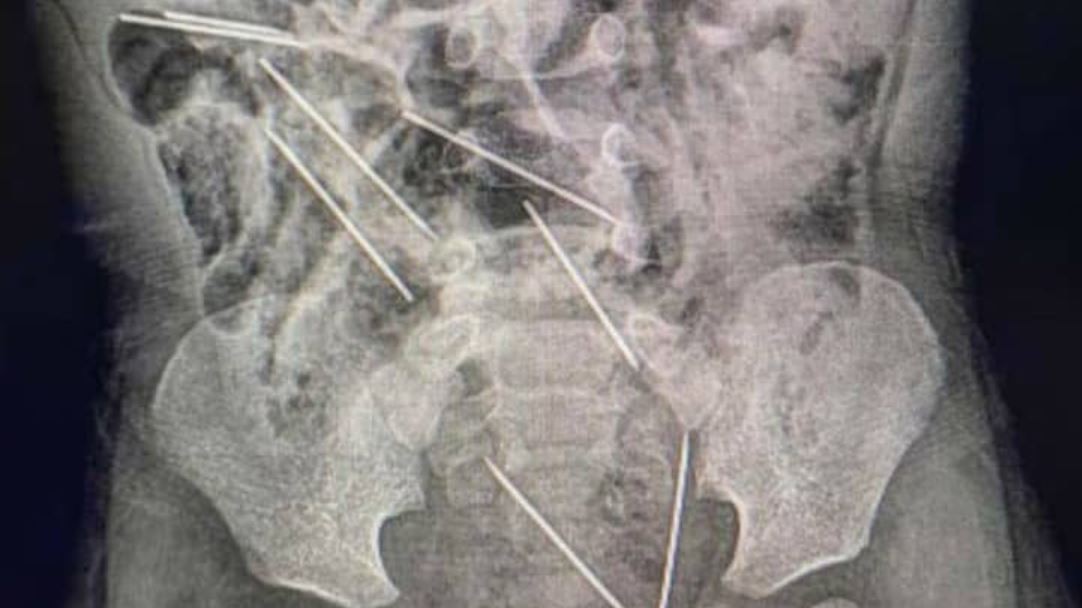

Los médicos le realizaron los estudios en los que detectaron la presencia de las agujas diversas partes de su cuerpo: dos en el peritoneo lado derecho, tres en el lado izquierdo, uno en la pared abdominal y las dos restantes entre la vejiga y el recto.

Tras varias horas de trabajo médico, lograron extraerlas todas. De acuerdo con los profesionales, al nene le lavaron el estómago y le quedó una pequeña lesión en el intestino delgado.